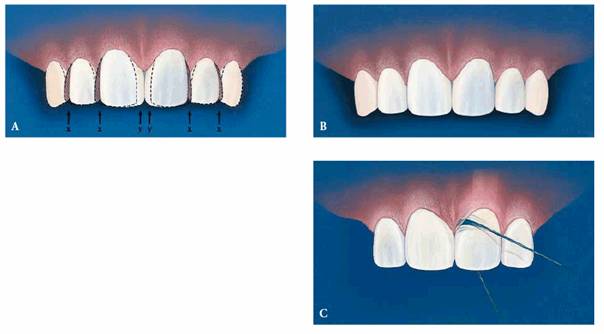

A schematic drawing of how this case was restored can be seen in Figures 23-11A

and B.

"X" denotes the distal surface of the central and lateral incisors,

which were reduced to compensate for the addition of composite resin to the

mesial surface of the teeth. This reduction of the distal surface helps to keep

the mesially bonded aspects ("Y") of the central incisors in proper

proportion. Any subgingival bonded areas must be meticulously contoured and

finished so that the patient can maintain good dental hygiene and tissue health

with the use of dental floss (Figure 23-11C

Figure 23-11A to C: (A) and (B) These drawings illustrate how the teeth of the patient in Figure 23-10 were restored to give a better proportioned smile (see text). (C) The shape of the bonding should be conducive to easy flossing.